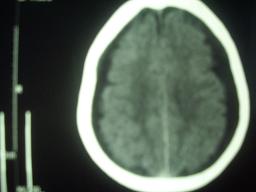

男,90岁,5天前曾摔倒,头颅并未受伤,今天突然头疼,但无呕吐!

ct结果怀疑双侧硬膜下积液!

外伤性硬膜下积液(traumatic subdural effusion, tse)又名外伤性硬膜下水瘤, tse好发于60岁以上老年人,这与老年人存在不同程度脑萎缩、硬膜下间隙增大有关。根据颅脑损伤病史,伤后头痛、头晕、恶心、呕吐等症状,及ct扫描表现为单侧或双侧颅内骨板侧低密度,呈弧形或新月形,与脑组织边界清楚,tse不难诊断

双侧硬膜下积液,个别病例随访观察可形成慢性硬膜下血肿,此例波及范围大,应警惕!